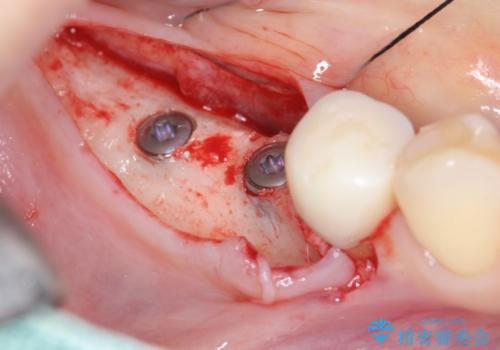

- 失ってしまった奥歯の咬合機能の回復を求めて来院されました。

骨の幅が十分にないのでインプラント治療に伴い、人工骨の造成を同時に計画します。

インプラントは高い確率で骨に結合し、しっかりとした咬合力を回復することができます。

長年安心してしっかりと噛んでいただけるよう今回は骨を増成する治療計画としました。